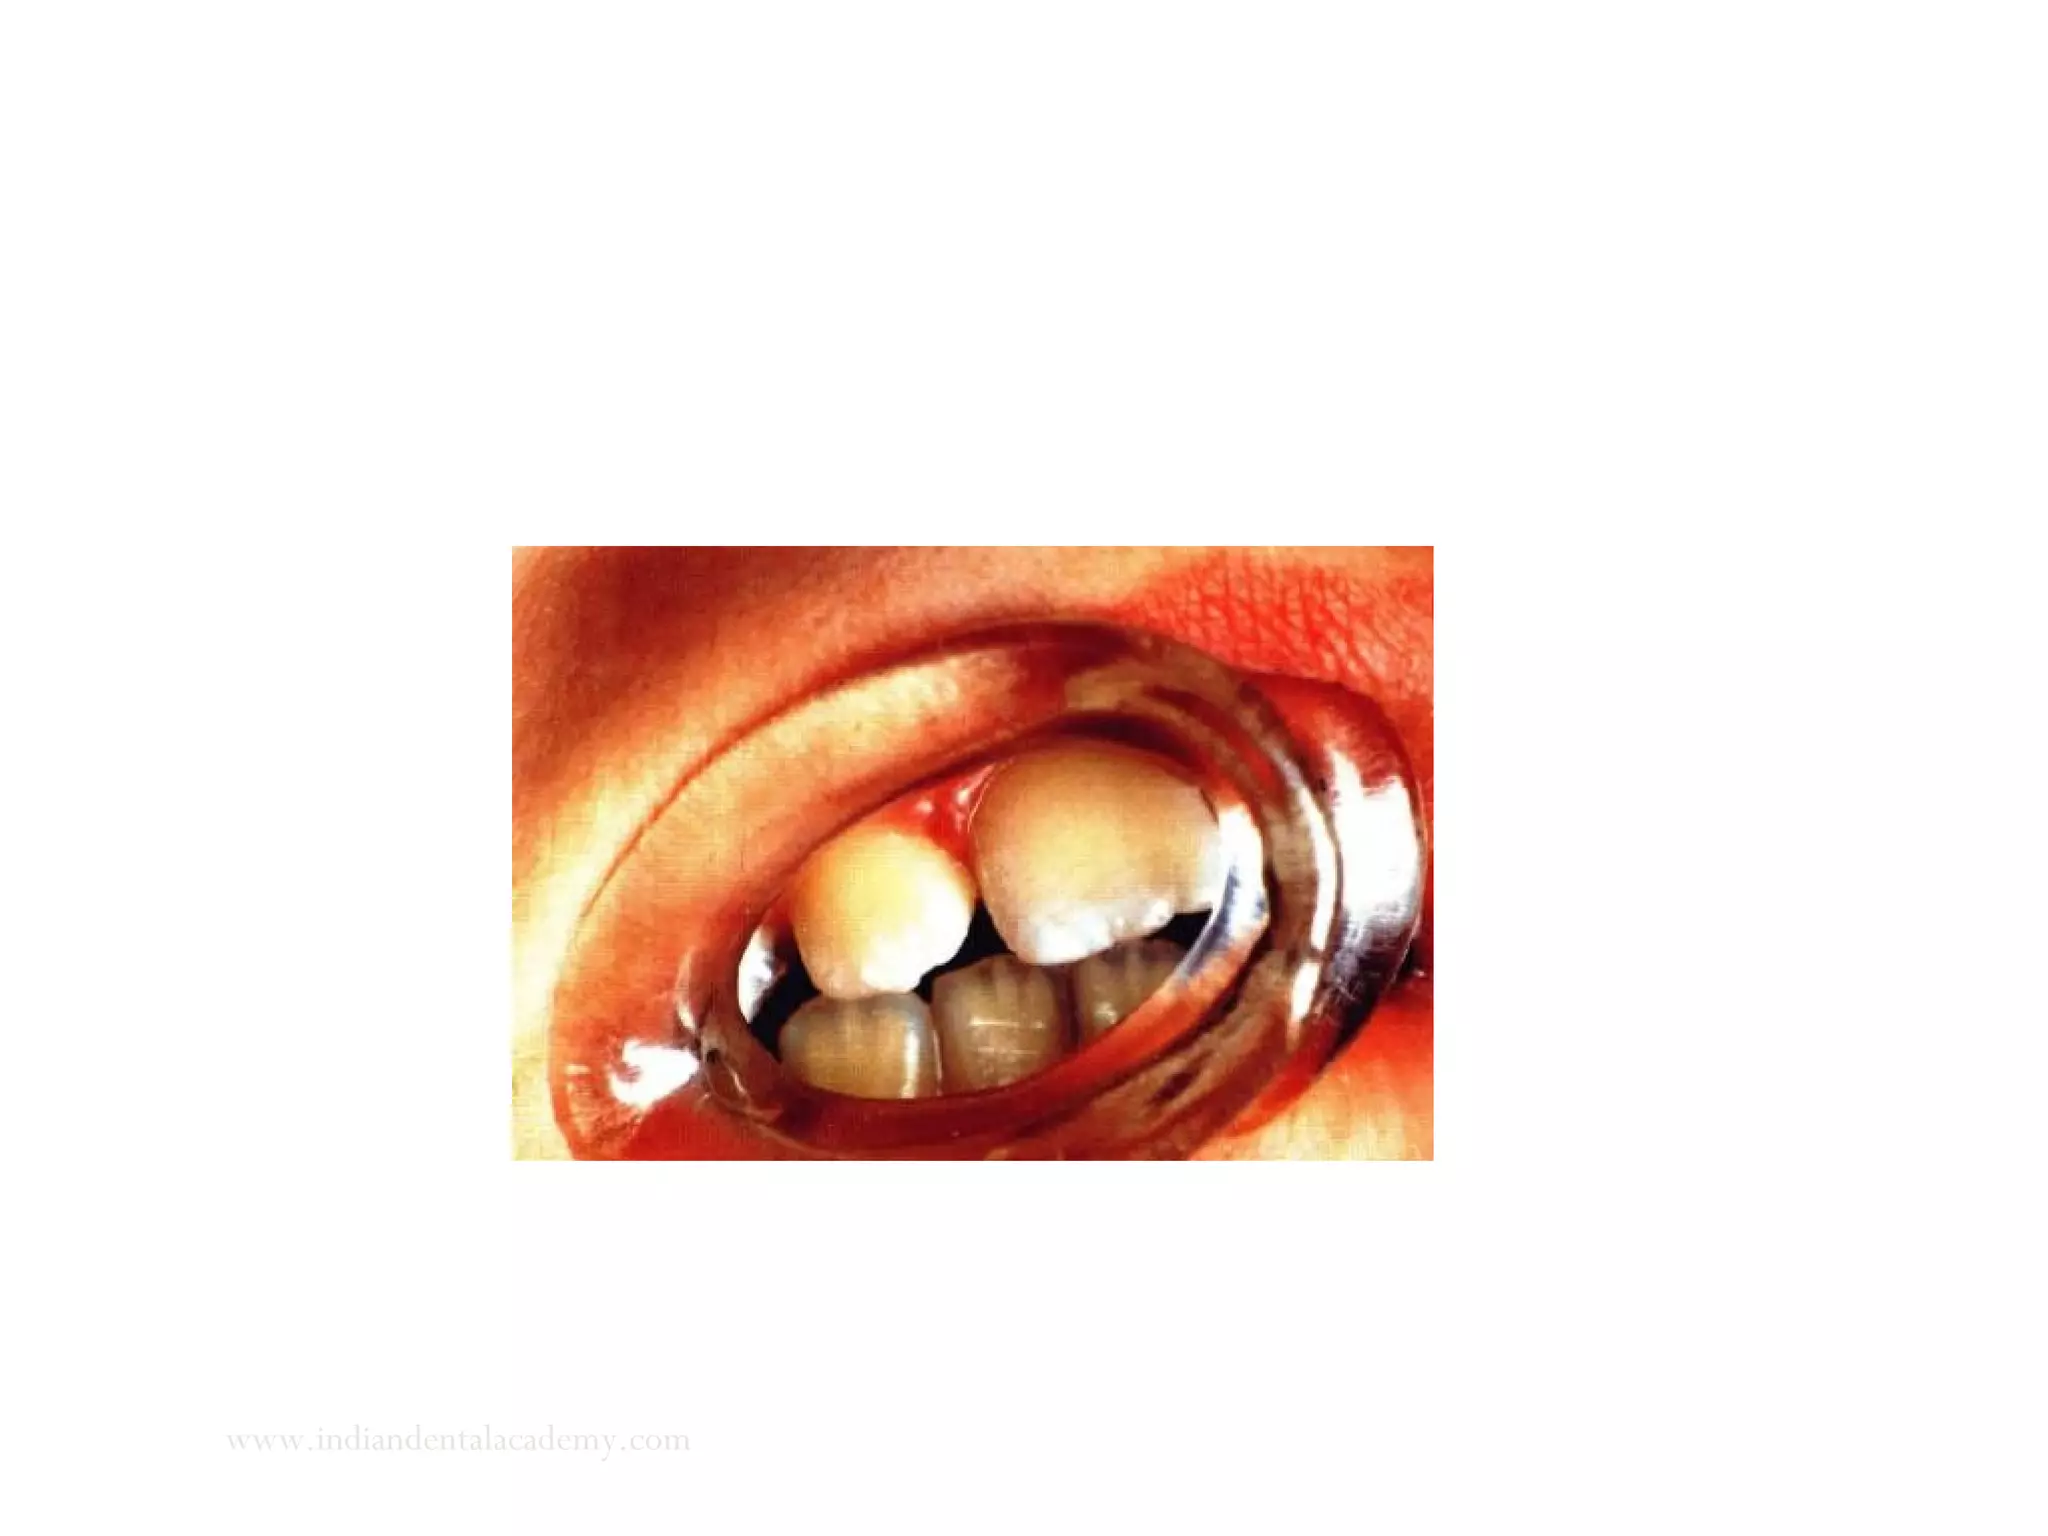

Evaluation of the path of closure from postural rest to occlusion in

vertical plane

True deep bite

www.indiandentalacademy.com

Pseudo deep overbite